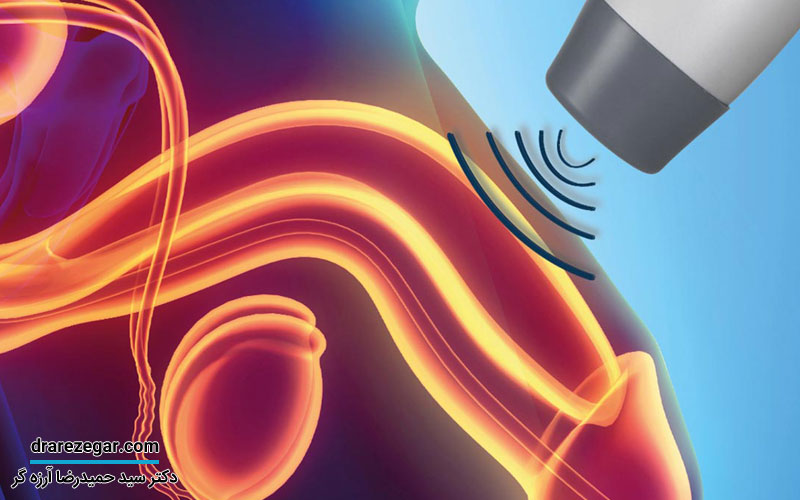

اگر گاهی احساس می کنید ادرارتان به طور کامل تخلیه نمی شود یا فشار و سنگینی در پایین شکم دارید، این علائم را نباید نادیده بگیرید. چنین نشانه هایی ممکن است مربوط به افتادگی مثانه باشند و اگر زود پیگیری نشوند، ممکن است باعث مشکلات بیشتری شوند. گاهی با چند روش ساده و مراقبت به موقع می توان جلوی پیشرفت این مشکل را گرفت. برای اینکه مطمئن شوید وضعیت مثانه تان طبیعی است و نیاز به درمان خاصی ندارید، بهتر است به پزشک متخصص مراجعه کنید. دکتر سید حمیدرضا آرزه گر، متخصص بیماری های کلیه و مجاری ادراری، با تجربه بالا در این زمینه، می توانند به شما کمک کنند تا دلیل مشکلات ادراری تان مشخص شود و راه های مناسب برای پیشگیری از افتادگی مثانه را پیدا کنید. برای مشاوره و تعیین وقت ویزیت، می توانید از طریق راه های ارتباطی موجود در سایت دکتر آرزه گر اقدام کنید و از راهکارهای تخصصی ایشان استفاده کنید.